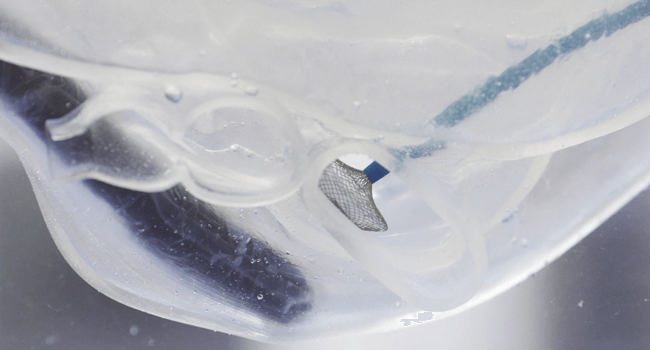

ASD/PFO Closureモデル

心房中隔欠損症を再現した心臓モデルです。透明素材を用いており、心腔内でのカテーテルの動きが外から確認できます。

ASD/PFO Closureモデル

心房中隔欠損症を再現した心臓モデルです。透明素材を用いており、心腔内でのカテーテルの動きが外から確認できます。